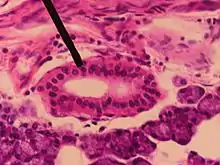

Striated duct in Parotid gland

A striated duct (Pflüger's ducts ) is a gland duct which connects an intercalated duct to an interlobular duct. It is characterized by the basal infoldings of its plasma membrane, characteristic of ion-pumping activity by the numerous mitochondria.[8][9] Along with the intercalated ducts, they function to modify salivary fluid by secreting HCO3 and K+ and reabsorbing Na+ and Cl using the Na-K pump and the Cl-HCO3 pump, making the saliva hypotonic.

Their epithelium can be simple cuboidal or simple columnar.[10]

Striated ducts are part of the intralobular ducts.

They are found in the submandibular gland,[11][12] sublingual duct, and the parotid gland, but are more developed in the parotid gland.[13]

They are not present in pancreas.